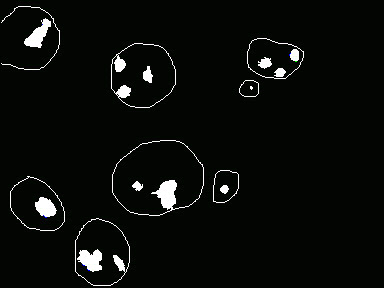

Figura 2. Imagen obtenida a partir de la figura 1 segmentando los núcleos con tinción AgNOR .

Figura 3. Imagen que contiene los contornos nucleares y AgNOR en su interior para contaje de estructuras y medida del área.